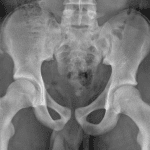

Age: 14

Sex: Male

Indication: Right hip injury

- Acute avulsion fracture of the right anterior superior iliac spine

Diagnosis

- ASIS avulsion fracture

Acute avulsion fracture of the right anterior superior iliac spine (ASIS).

No joint malalignment.

- Pelvic avulsion fractures can be very easy to miss, so it is important to look closely for them, particularly in young athletes